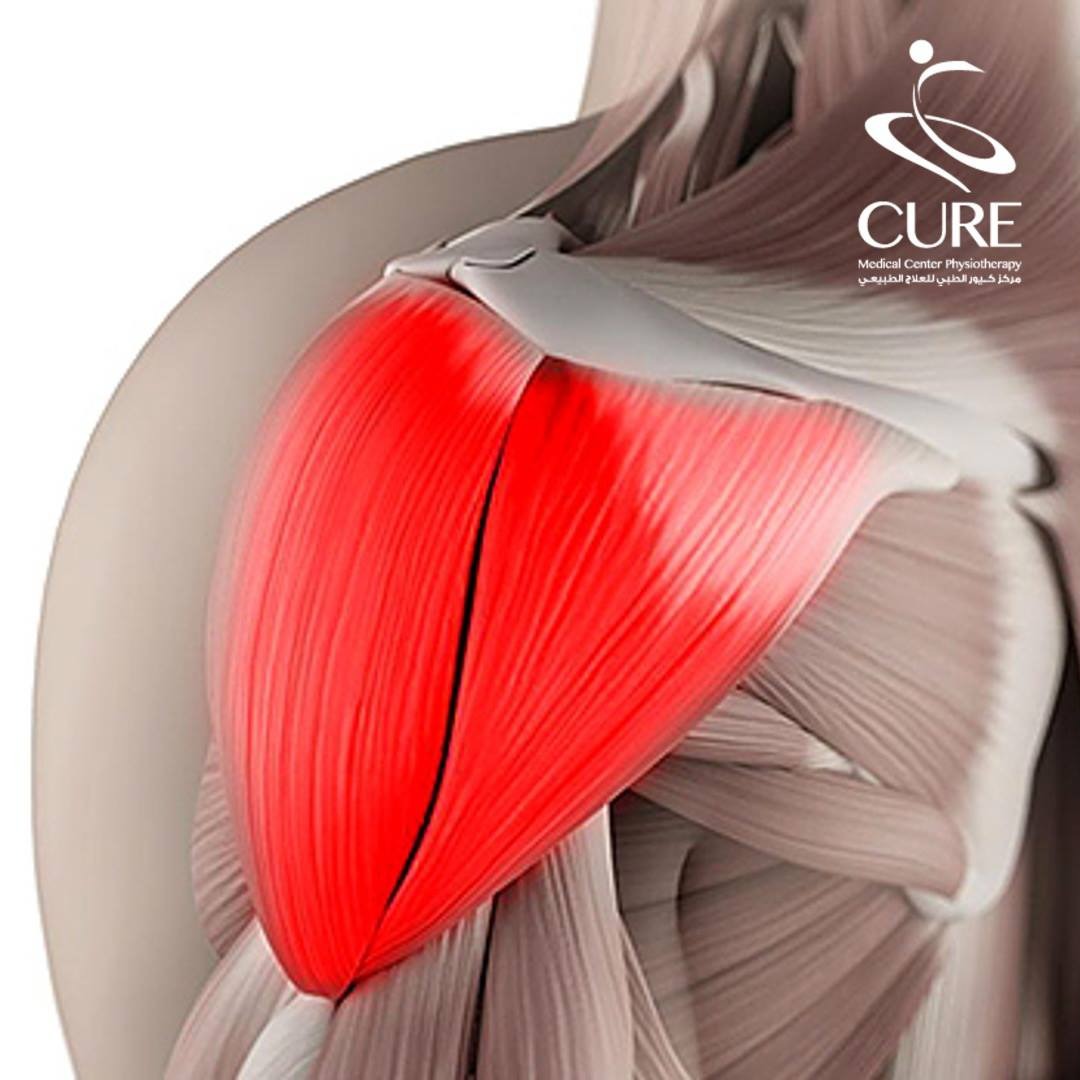

Фотографии поддельтовидной мышцы плечевого сустава